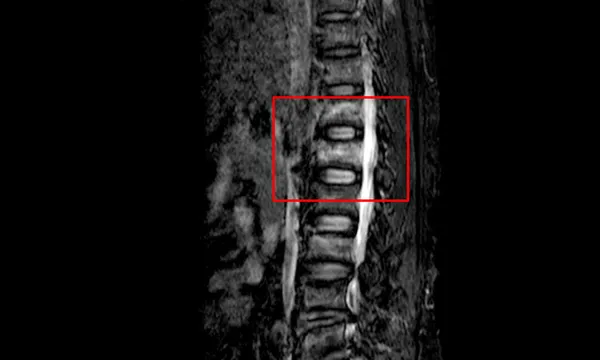

Sau khi ngã, bệnh nhân đau vai nhiều, vận động khó khăn và phải nhập viện cấp cứu. Hình ảnh chụp cắt lớp vi tính cho thấy, bệnh nhân bị vỡ xẹp nhiều đốt sống (L1, L3), gãy kín xương sườn (7,8, 9 bên phải và 5,6,7,8,9 bên trái).

Bác sĩ chuyên khoa II Phạm Minh Phương - Trưởng Khoa Ngoại thần kinh cho biết, chấn thương cột sống thắt lưng là thương tổn có thể để lại những hậu quả nặng nề như gây mất vững cột sống và thương tổn dẫn đến liệt 2 chi dưới.